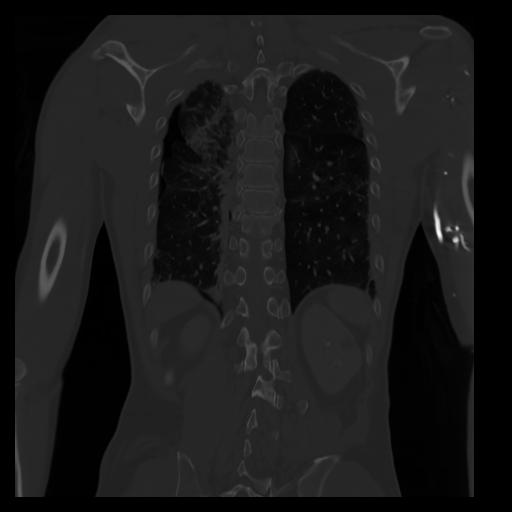

29 CUERPO,CE,Coronal,3.000,CUERPO,Coronal,